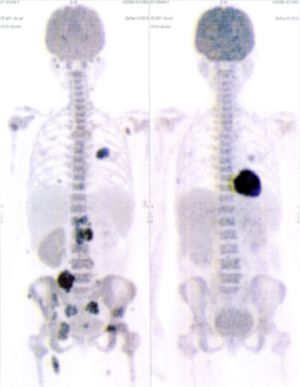

CASE NO: 4 (PROSTATE CANCER)

A middle-aged man with castration resistant prostate cancer and massive bone metastases, failed all currently available cancer treatment, including with the new and expensive drug XTANDI. After a few treatment, most of the bone metastases went into remission, and the remaining ones are less active. Treatment will continue. Cases no: 3 and 4 show that terminal prostate cancer today can be cured with our new cancer treatment.